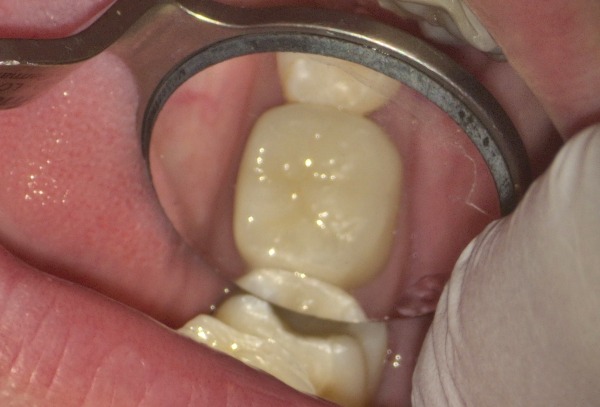

6日目 セラミックの被せ物と詰め物を装着しました。

治療後の様子

これまで患者様は、治療に対する要望や不安を歯科医師になかなか相談できず、お口の中の状態がよくわからなかったそうです。今回、口腔内カメラで撮影しながら治療の過程を英語で説明していきました。大きな画面ではっきりと見やすく、説明を聞いて納得しながら治療を受けられたことが嬉しいとおっしゃっていました。